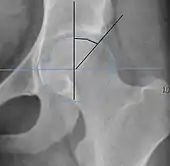

Measurements of impingement on X-ray.[notes 1][20]

MeasurementImageTargetNormal value

Alpha angle

Measured in 45° Dunn view.

Degree of bulging of the femoral head-neck junction: In normal conditions there is a symmetric concave contour at the junction of the femoral head and neck. Loss of this concavity or bone bulging may lead to cam type impingement. The degree of this deformity can be measured by the alpha angle. Although it can be measured in the cross-lateral view, the 45° Dunn view is considered more sensitive and the frog leg view more specific in determining pathologic values.

• Normal: ≤68° in men, ≤50° in women

• Borderline: 69° to 82° in men, 51° to 56° in women

• Pathological: ≥83° in men and ≥57° in women